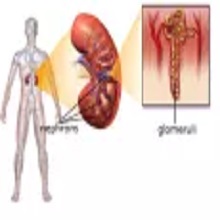

Пијелонефртитис представља запаљење ткива бубрега које траје (бубрежне карлице, чашица и каналића). По дужини трајања дели се на акутни и хронични. |

| У зависности од силе која је изазвала трауму, повреде бубрега делимо на оне изазване тупом силом (пад са висине, повреде задобијене у саобраћајном удесу и сл.) и повреде настале дејством оштрих предмета (нож, сечива). Ове повреде могу бити изоловане, или удружене са повредама других органа. Велику групу чине јатрогене повреде настале у току извођења перкутане биопсије бубрега, пласирања нефростоме или литотрипсијe. |

| Већина болесника који имају срчану слабост пре или касније развије и бубрежну слабост, исто важи и за обрнуту варијанту. То значи да болест једног од та два органа временом доводи до погоршања функције другог органа и тако настаје кардио - ренални или рено - кардијални синдром. Зато је врло важно да приступ болесницима буде мултидисциплинарни, да се у лечењу таквих пацијената ангажује како кардиолог, тако и нефролог. |

| Терминална бубрежна слабост представља крајњи стадијум акутних као и хроничних бубрежних болести.Терминална бубрежна слабост је стадијум бубрежне болести где је, ради спасавања пацијентовог живота, неопходна примена неких од метода замене бурежне функције, нека од врста дијализе или трансплантација бубрега. |

Главобоља и повишен крвни притисак били су први симптоми које је осетио Павловић Милан. Када су постали учестали, јавио се доктору Горану Војиновићу, нефрологу у Општој болници Панчево, који га је упутио на испитивање у Клинички центар, где је утврђено да су бубрези пред отказивањем. |

„Када бубрези откажу неопходна је хемодијализа од које и зависи какав ће бити квалитет живот сваком пацијенту. Постоје квалитетније методе дијализе које су скоро као да је пацијент добио буберг. Ова метода била је и раније доступна само млађим пацијентима сада је захваљући Републичком фонду за здравствено осигурање доступна већем броју пацијента, што је од великог значаја", истиче нефролог др Горан Војиновић шеф одсека Хемодијализе. |

| Бубрези су парни органи, који представљају централни део уринарног система. Смештени су у ретроперитонеалном простору на задњем зиду абдомена, и налазе се са обе стране кичменог стуба. Десни бубрег, потиснут јетром, постављен је мало ниже у односу на леви. |

Нажалост болест брзо напредује и за кратко време бубрези отказују зато је погрешно одлагати хемодијализу. Убедити младог човека који још има снаге је тешко, али како време одмиче пацијент сам осећа замор, не може да спава, бори се за дах и онда схватају да морају себи да помогну. |

| Хронична бубрежна слабост је прогресивно оштећење свих бубрежних функција које води ка терминалној фази болести где симптоматска терапија није довољна. Тада је за продужетак живота неопходно применити једну од метода замене бубрежне функције (хемодијализа, перитонеумска дијализа и трансплантација бубрега). |